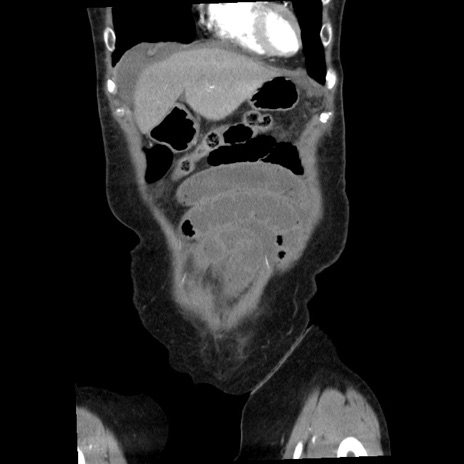

症例1(冠状断像)

【症例】80歳代女性

【主訴】腹痛

【現病歴】8時間前から腹痛あり来院。

【既往歴】糖尿病、脂質異常症、子宮体癌にて子宮全摘術

【身体所見】意識清明・会話良好だが腹痛で苦悶様、全腹部にわたって反跳痛と圧痛あり

【データ】WBC 13600、CRP 0.14、LDH 224、CK 90